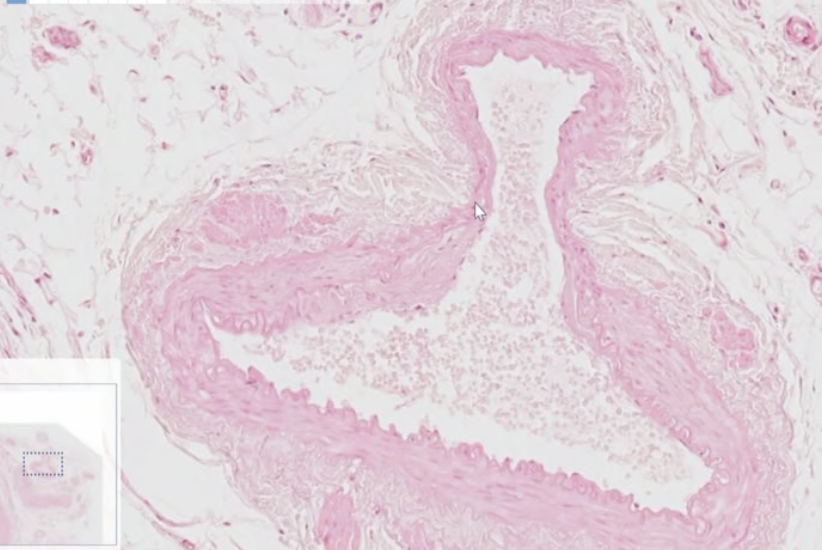

Quoi comme vx?

Artère (même si elle est pas ronde)

=> Musculature compacte et homogène sur tout le pourtour